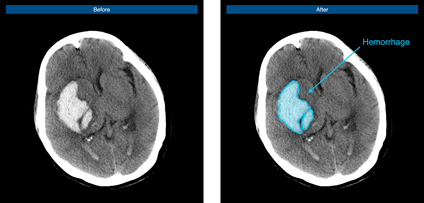

腦出血病例示意圖

腦血管疾病領(lǐng)域作為推想醫(yī)療早期布局的重要疾病領(lǐng)域之一,在近年的北美放射協(xié)會(huì)年會(huì)(RSNA)上,公司便展示了首款腦卒中AI在研產(chǎn)品,通過不斷研發(fā)和快速迭代“進(jìn)化”,該產(chǎn)品已可快速判別是否存在出血、高效標(biāo)注出血病變、準(zhǔn)確定位和勾畫出血區(qū)域、快速自動(dòng)計(jì)算出血體積,從而提升醫(yī)生的診斷速度,完善院端急救場景的智能分診和流程管理,并最終為腦卒中患者贏得救治黃金期。